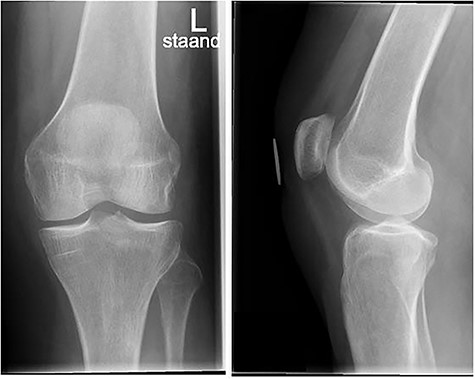

A conventional radiograph of the left knee showed no abnormalities (Fig. 1). An MRI scan was performed that confirmed an ACL tear accompanied by a grade 1 MCL tear, a lateral meniscal tear and a small incomplete fracture of the posteromedial tibia plateau (Fig. 2a–c). Arthroscopy of the knee was scheduled because of catching with persistent limited range of motion despite physical therapy 10 weeks after initial trauma.

Conventional radiograph of the left knee shows no abnormalities.